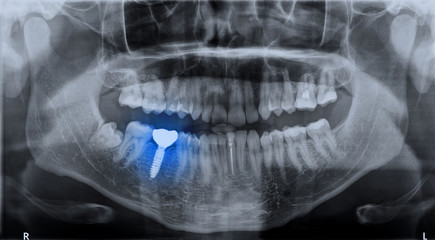

디지털 가이드 임플란트는 3D CT 스캔과 특수 소프트웨어를 사용하여 정확한 임플란트 위치를 계획하고 시술하는 방법입니다. 이 기술은 높은 정확도로 합병증 위험을 감소시키고, 시술 시간을 최대 50%까지 단축시킬 수 있으며, 덜 침습적인 시술로 회복 기간을 단축시킵니다.

비용 효율성 측면에서, 초기 비용은 일반 임플란트 대비 20-30% 높을 수 있지만, 정확한 시술로 인한 합병증 감소와 재시술 필요성 감소로 장기적으로 10-15% 비용 절감이 가능합니다.

3. 네비게이션 임플란트 시스템

네비게이션 임플란트 시스템은 실시간으로 임플란트 식립 위치를 안내하는 시스템입니다. 이 기술은 실시간 정확도 확인으로 0.5mm 이내의 오차 범위를 달성할 수 있고, 시술 중 조정이 가능하여 성공률을 5-10% 향상시킬 수 있습니다.

비용 효율성 측면에서, 시스템 도입 비용이 3,000-5,000만원 소요되지만, 정확한 시술로 인한 재시술 감소(약 7-10%)와 시술 시간 단축(평균 30%)으로 장기적 비용 절감이 가능합니다.